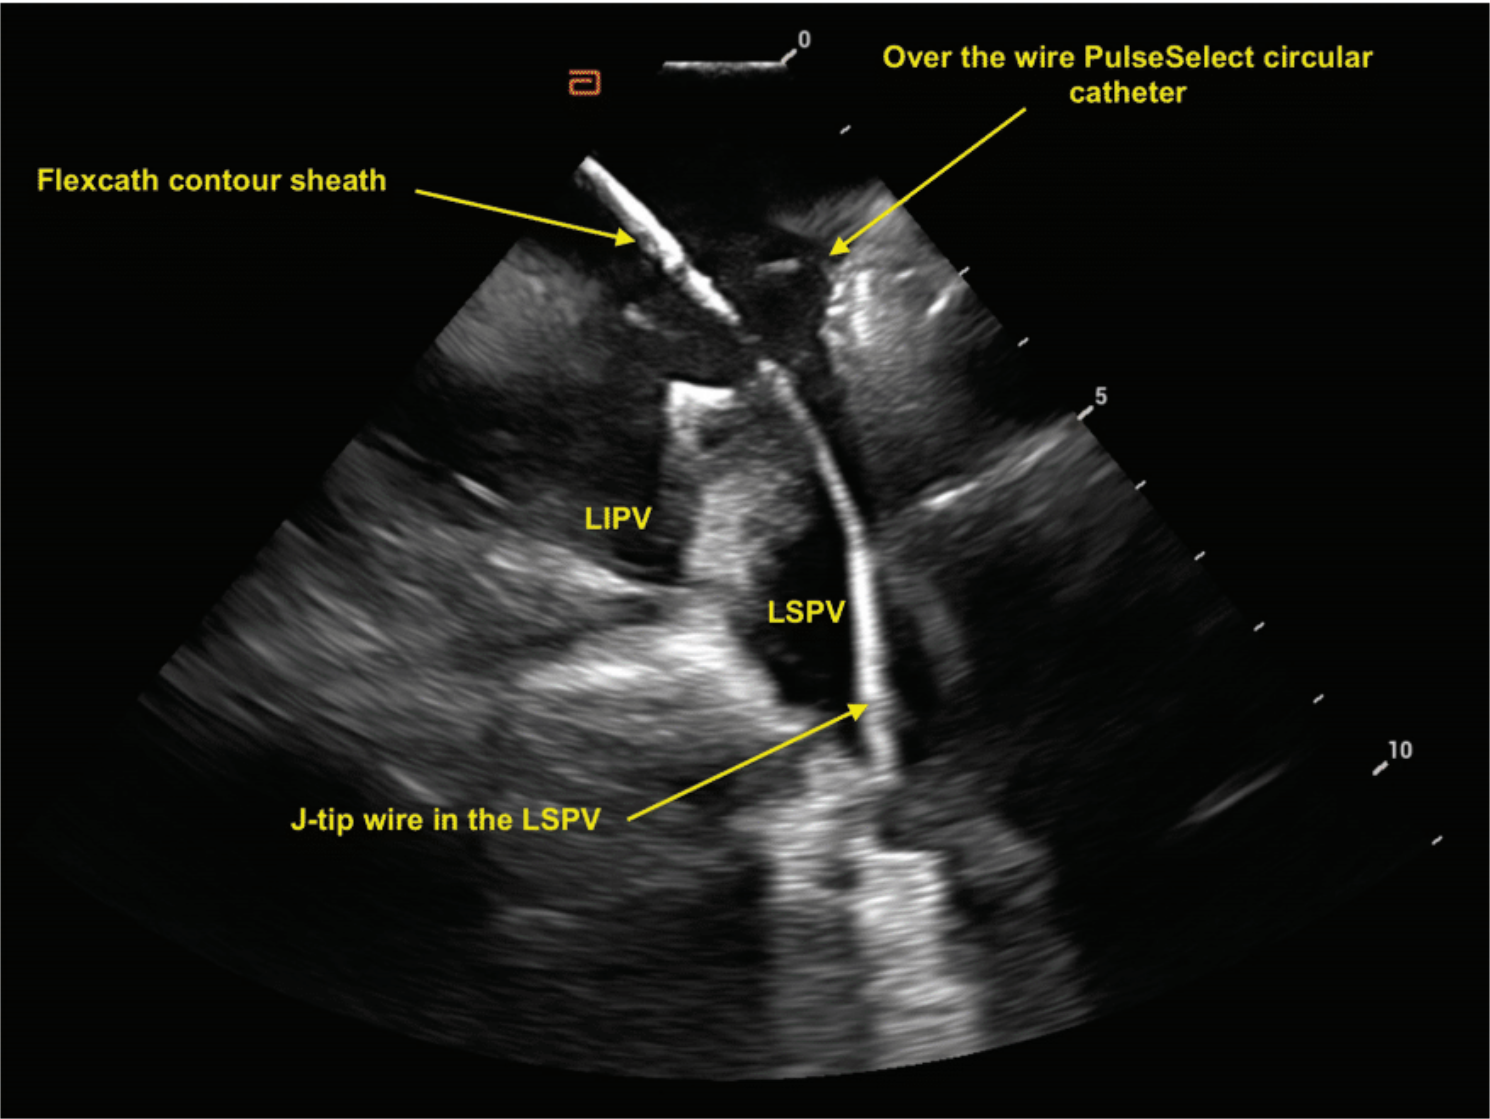

While all 4 PVs could be seen from the RA, excellent visualization of the PVs was obtained when the ICE catheter was advanced into the LA. To achieve this end, the ICE catheter was placed through the hole created by the transseptal puncture. Following transseptal sheath exchange, the pigtail wire was left in the mid LA. The FlexCath Contour-dilator assembly was then pulled back into the RA while keeping the wire in the LA. Next, anterior tilt was placed so that the tip of the ICE catheter approximated the entry point of the wire into the transseptal hole. The ICE catheter was then advanced from the RA to LA next to the wire through the same hole (Figure 6). The FlexCath-dilator assembly was advanced into the LA, and the dilator and wire were then removed. With the ICE catheter in the LA, placing posterior tilt resulted in improved visualization of the left PVs. With the posterior tilt removed, clockwise rotation resulted in visualization of the right-sided PVs.

During PFA, the integration of ICE and mapping systems allows for accurate registration of the wire and catheter position within the 3D map, obviating the need for fluoroscopic verification (Figure 7). The map shift is minimal when the coronary sinus catheter is used as a reference for the map. ICE provides real-time, high-resolution visualization of intracardiac structures, enabling precise catheter manipulation and accurate identification of anatomical landmarks. Additionally, the continuous feedback from ICE allows for real-time assessment of adequate catheter contact with the atrial tissue (Figure 8), which is crucial for a successful PFA procedure. The mapping system provides detailed spatial information, enabling the identification and localization of PV ostia, the LA posterior wall, and other critical sites. This spatial precision is crucial in PFA, where lesion sets must be carefully tailored to achieve complete and durable PVI while avoiding gaps that could lead to AF recurrence. The PulseSelect PFA catheter is designed with 20° forward tilted array to ensure contact where the 5th electrode is the first electrode to contact the tissue. Our workflow includes highlighting electrode 5 on our mapping system and tagging it as a lesion once a satisfactory PFA application is delivered. The catheter is then rotated 90° to overlap lesion set and electrode 5 is tagged in its new location. In our stepwise ostial-antral approach, at least 4 ostial and 4 antral applications are applied with electrode 5 tagged at the 12, 3, 6, and 9 o’clock positions in the vein to ensure contiguous PVI (Figure 9).